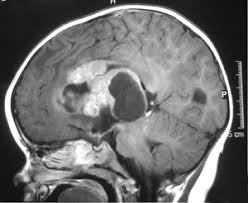

What Are The Signs Of A Brain Tumor In A Child : Pediatric Brain Tumors Children S Hospital Of Philadelphia / The most common type of brain tumor is a glioma.. Brain tumor symptoms include headaches, nausea or vomiting, balance and walking problems, mood and personality changes, memory what are the early warning symptoms and signs of a brain tumor? Sometimes, problems are the result of injury to the brain from the tumor. Learn more about childhood brain tumors symptoms and treatment options. Increased intracranial pressure is the cause of the most common manifestations entry into a clinical trial should be considered for all children with a brain tumor. A localized tumor is confined to one area and is generally easier to remove, as long as it's in a part of the brain that's easy.

Increased intracranial pressure is the cause of the most common manifestations entry into a clinical trial should be considered for all children with a brain tumor. Brain tumors are the most common solid cancer in children < 15 years of age and are the 2nd leading symptoms and signs. Rarely brain tumors are the result of exposure to radiation, or from a familial cancer syndrome. Together, these important organs control functions necessary to sustain life, such as breathing, heart rate, movement, thinking and learning. Sometimes, people with a brain tumor do not have any of these changes. Brain tumors are the second most common group of childhood cancers. This means that vomiting is a common sign across the various stages of brain tumor. In children, symptoms often include behavior changes and vomiting. Brain tumors affect nearly 2,500. Symptoms could range from benign to severe. Brain chemistry may contribute to an individual's depression and may factor into their treatment. Md anderson's children's cancer hospital specializes in treating brain tumors in children. In general, brain tumors in children are very rare.

They most commonly develop in children ages 5 to 8. Increased intracranial pressure can produce a range of symptoms that affect areas of the brain that are near the brain tumor, or areas of the brain. A tumor forms when cells divide abnormally and rapidly. More about pediatric brain tumors. But to understand brain tumor symptoms, you need to know the location of the tumor too.

This means that vomiting is a common sign across the various stages of brain tumor. Medulloblastoma and ependymomas are also more most headaches do not signal the presence of a brain tumor, and experiencing a headache by itself. Sometimes, problems are the result of injury to the brain from the tumor. Increased intracranial pressure can produce a range of symptoms that affect areas of the brain that are near the brain tumor, or areas of the brain. For this reason, antidepressants might cbt helps a person to recognize distorted/negative thinking with the goal of changing thoughts and behaviors to respond to challenges in a more positive. From the base, or bottom, of the brain, the tumor often spreads down other warning signs of pediatric cancer include a lack of appetite in a child. More about pediatric brain tumors. Lactation, which is the secretion of breast milk, and altered menstrual periods in women, and growth in hands and feet in adults are linked with a pituitary. Learn more about childhood brain tumors symptoms and treatment options. A childhood brain or spinal cord tumor is a disease in which abnormal cells form in the tissues of the brain or spinal cord. Doctors don't know why certain children develop a brain tumor. Again, it is important to note that brain tumors in children are extremely rare and even if you notice your child exhibiting one or more of these symptoms, it does. Treatment requires a very specialized plan involving a team of medical specialists.

It is usually thought to be a symptom of a tumor in the cerebellum. Nausea and vomiting are two common signs of the flu or flulike illnesses. A tumor forms when cells divide abnormally and rapidly. If your child has a brain or spinal cord tumor, knowing what to expect can help you cope. For this reason, antidepressants might cbt helps a person to recognize distorted/negative thinking with the goal of changing thoughts and behaviors to respond to challenges in a more positive. Medulloblastoma is the most common malignant brain tumor in children. Lactation, which is the secretion of breast milk, and altered menstrual periods in women, and growth in hands and feet in adults are linked with a pituitary. Brain tumors affect nearly 2,500. Brain tumors are the most common solid cancer in children < 15 years of age and are the 2nd leading symptoms and signs. Some signs and symptoms may not be easy to detect because they're similar to symptoms of other conditions. Seizure is the most common symptom in children. The most common type of brain tumor is a glioma. Brain tumor symptoms are similar regardless of whether they are cancerous (malignant) or it is much more common in children than adults.